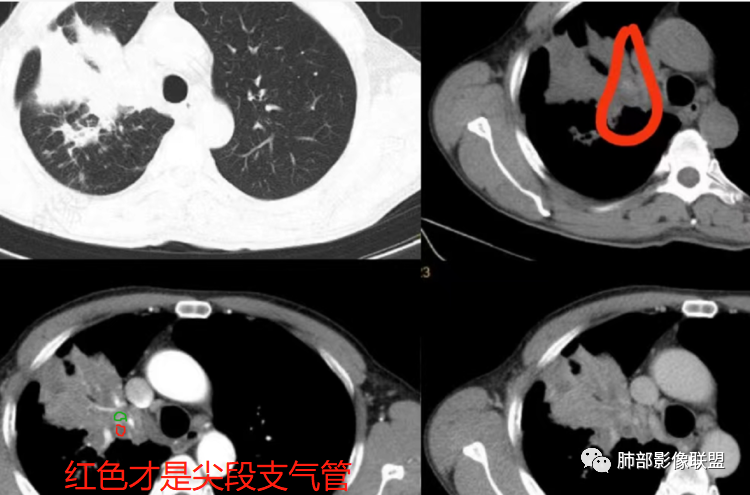

这是炎性的,支气管壁弥漫增厚,近端腔狭窄

这是肺癌的

这是腔内肺癌的

南边:

1、局部占位效应,支气管往往增大,而不是支气管狭窄

2、支气管壁破坏、不连续,腔外侵犯

3、占位效应大,局部肺动脉受压外移或侵犯